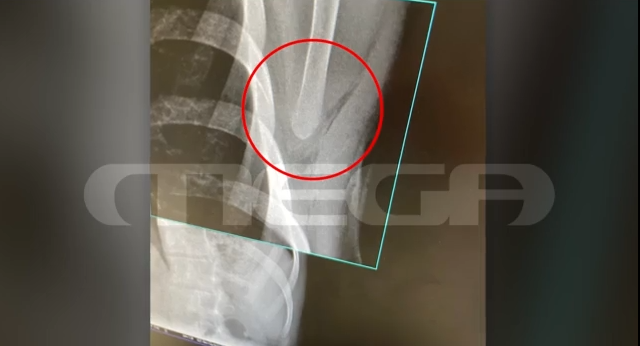

Το τραύμα του ήταν βαθύ, όπως αποτυπώνεται και στην ακτινογραφία.